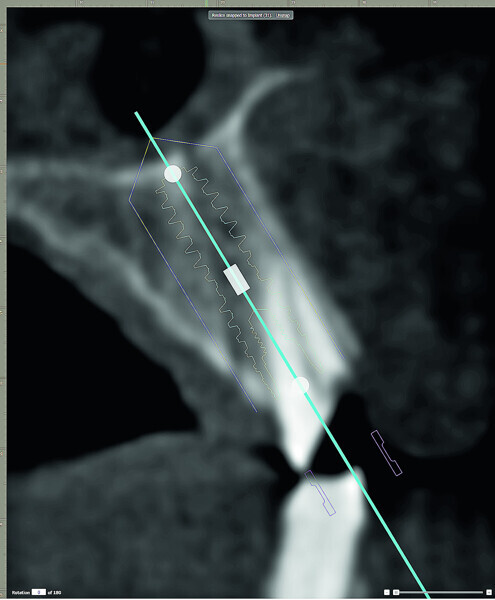

Fig. 3: Cross-sectional slice revealing the trajectory of the maxillary alveolus vs the trajectory of the root when planning for an implant.